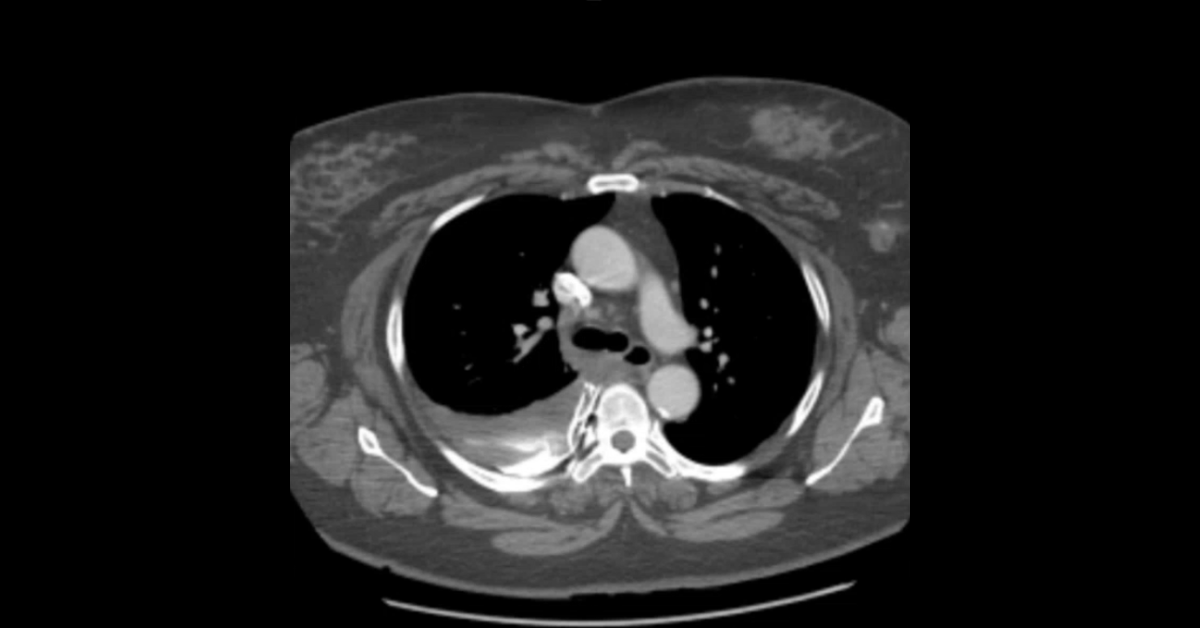

A collection of thoracic CT cases demonstrating a variety of pulmonary and mediastinal injuries.

1. Learn the breadth of lung injuries possible in trauma.

2. Understand the importance of identifying ankylosing spondylitis in trauma patients.

3. Identify the specific vessel source of mediastinal hemorrhage.